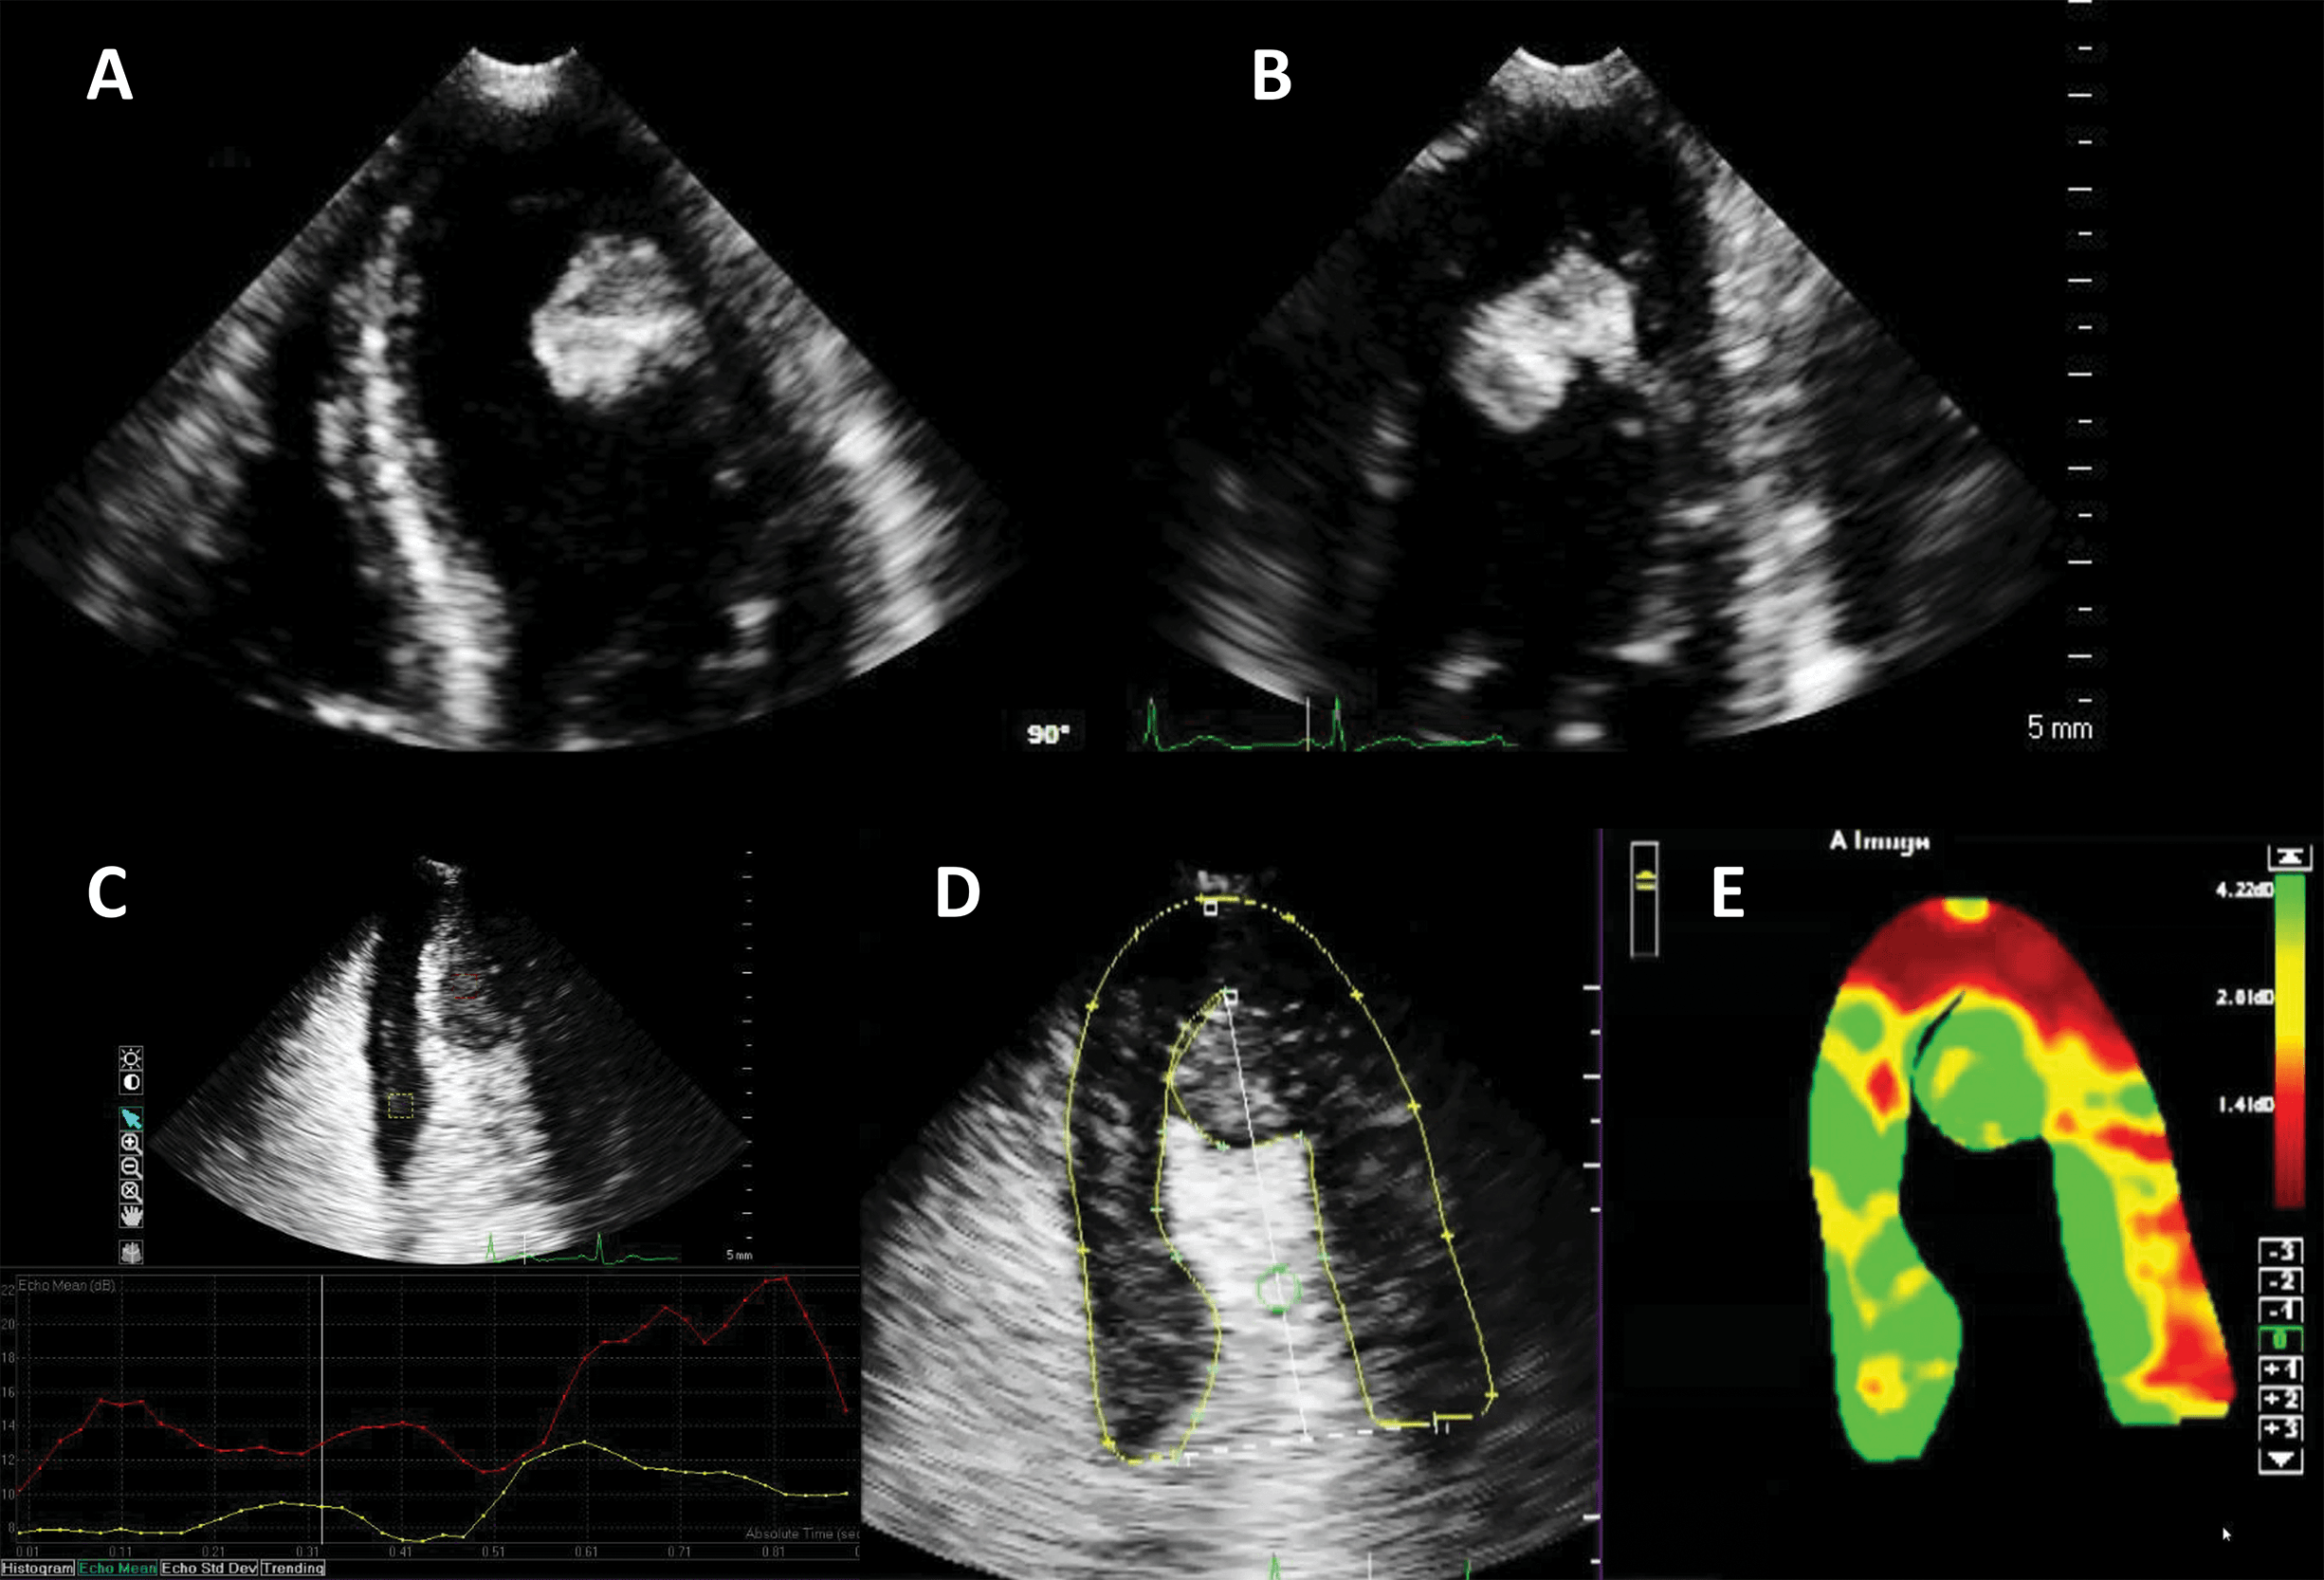

UEA have largely been used in the detection of LV thrombi [76, 77, 78]. This is in fact an application of the LVO method, enhancing the delineation between the wall, cavity and the thrombus mass (Fig. 10, Ref. [79]). However, prognostic implications for small mural thrombi are not clear. Myocardial perfusion detection, as described above, may help to diagnose small intracardiac or even intramural masses, by the presence and the dynamics of the vascularization inside the mass [80]. By adding a quantitative approach, it may even be possible to differentiate not only thrombi from tumors, but also benign from malignant tumors [79] (Fig. 11, Ref. [79]).

Fig. 11.Hyperechoic and hypermobile mass in a normal LV. The image quality is good, and the mass is hyperechoic. (A) 4-chambers view. (B) 2-chambers view. (C) Signal intensity quantification after a flash-replenishment cycle. The replenishment of the mass is similar to the interventricular septum, but with higher intensity, signalling the presence of a capillary vascularisation, with a higher density than the myocardium. (D,E) Parametric map of signal intensity, demonstrating the same features of the mass. In this patient the mass was finally diagnosed as a hypervascular metastasis from a lung carcinoma. Images modified with permission from Strachinaru et al. [79].